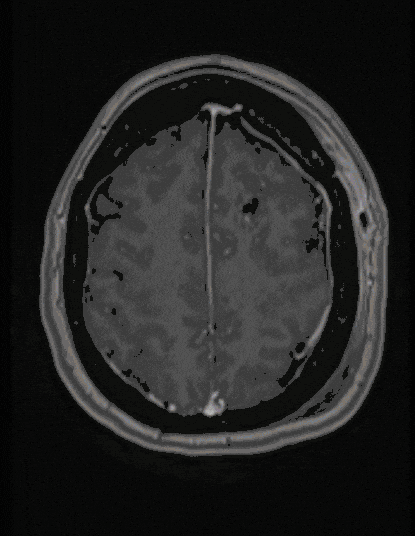

Astrocytoma

Astrocytomas are usually benign tumors with a largely good prognosis and slow growth. However, they can develop into aggressive malignant tumors even after years. Therefore, complete microsurgical removal is usually considered. Pilocytic astrocytoma of childhood represents a special benign form.